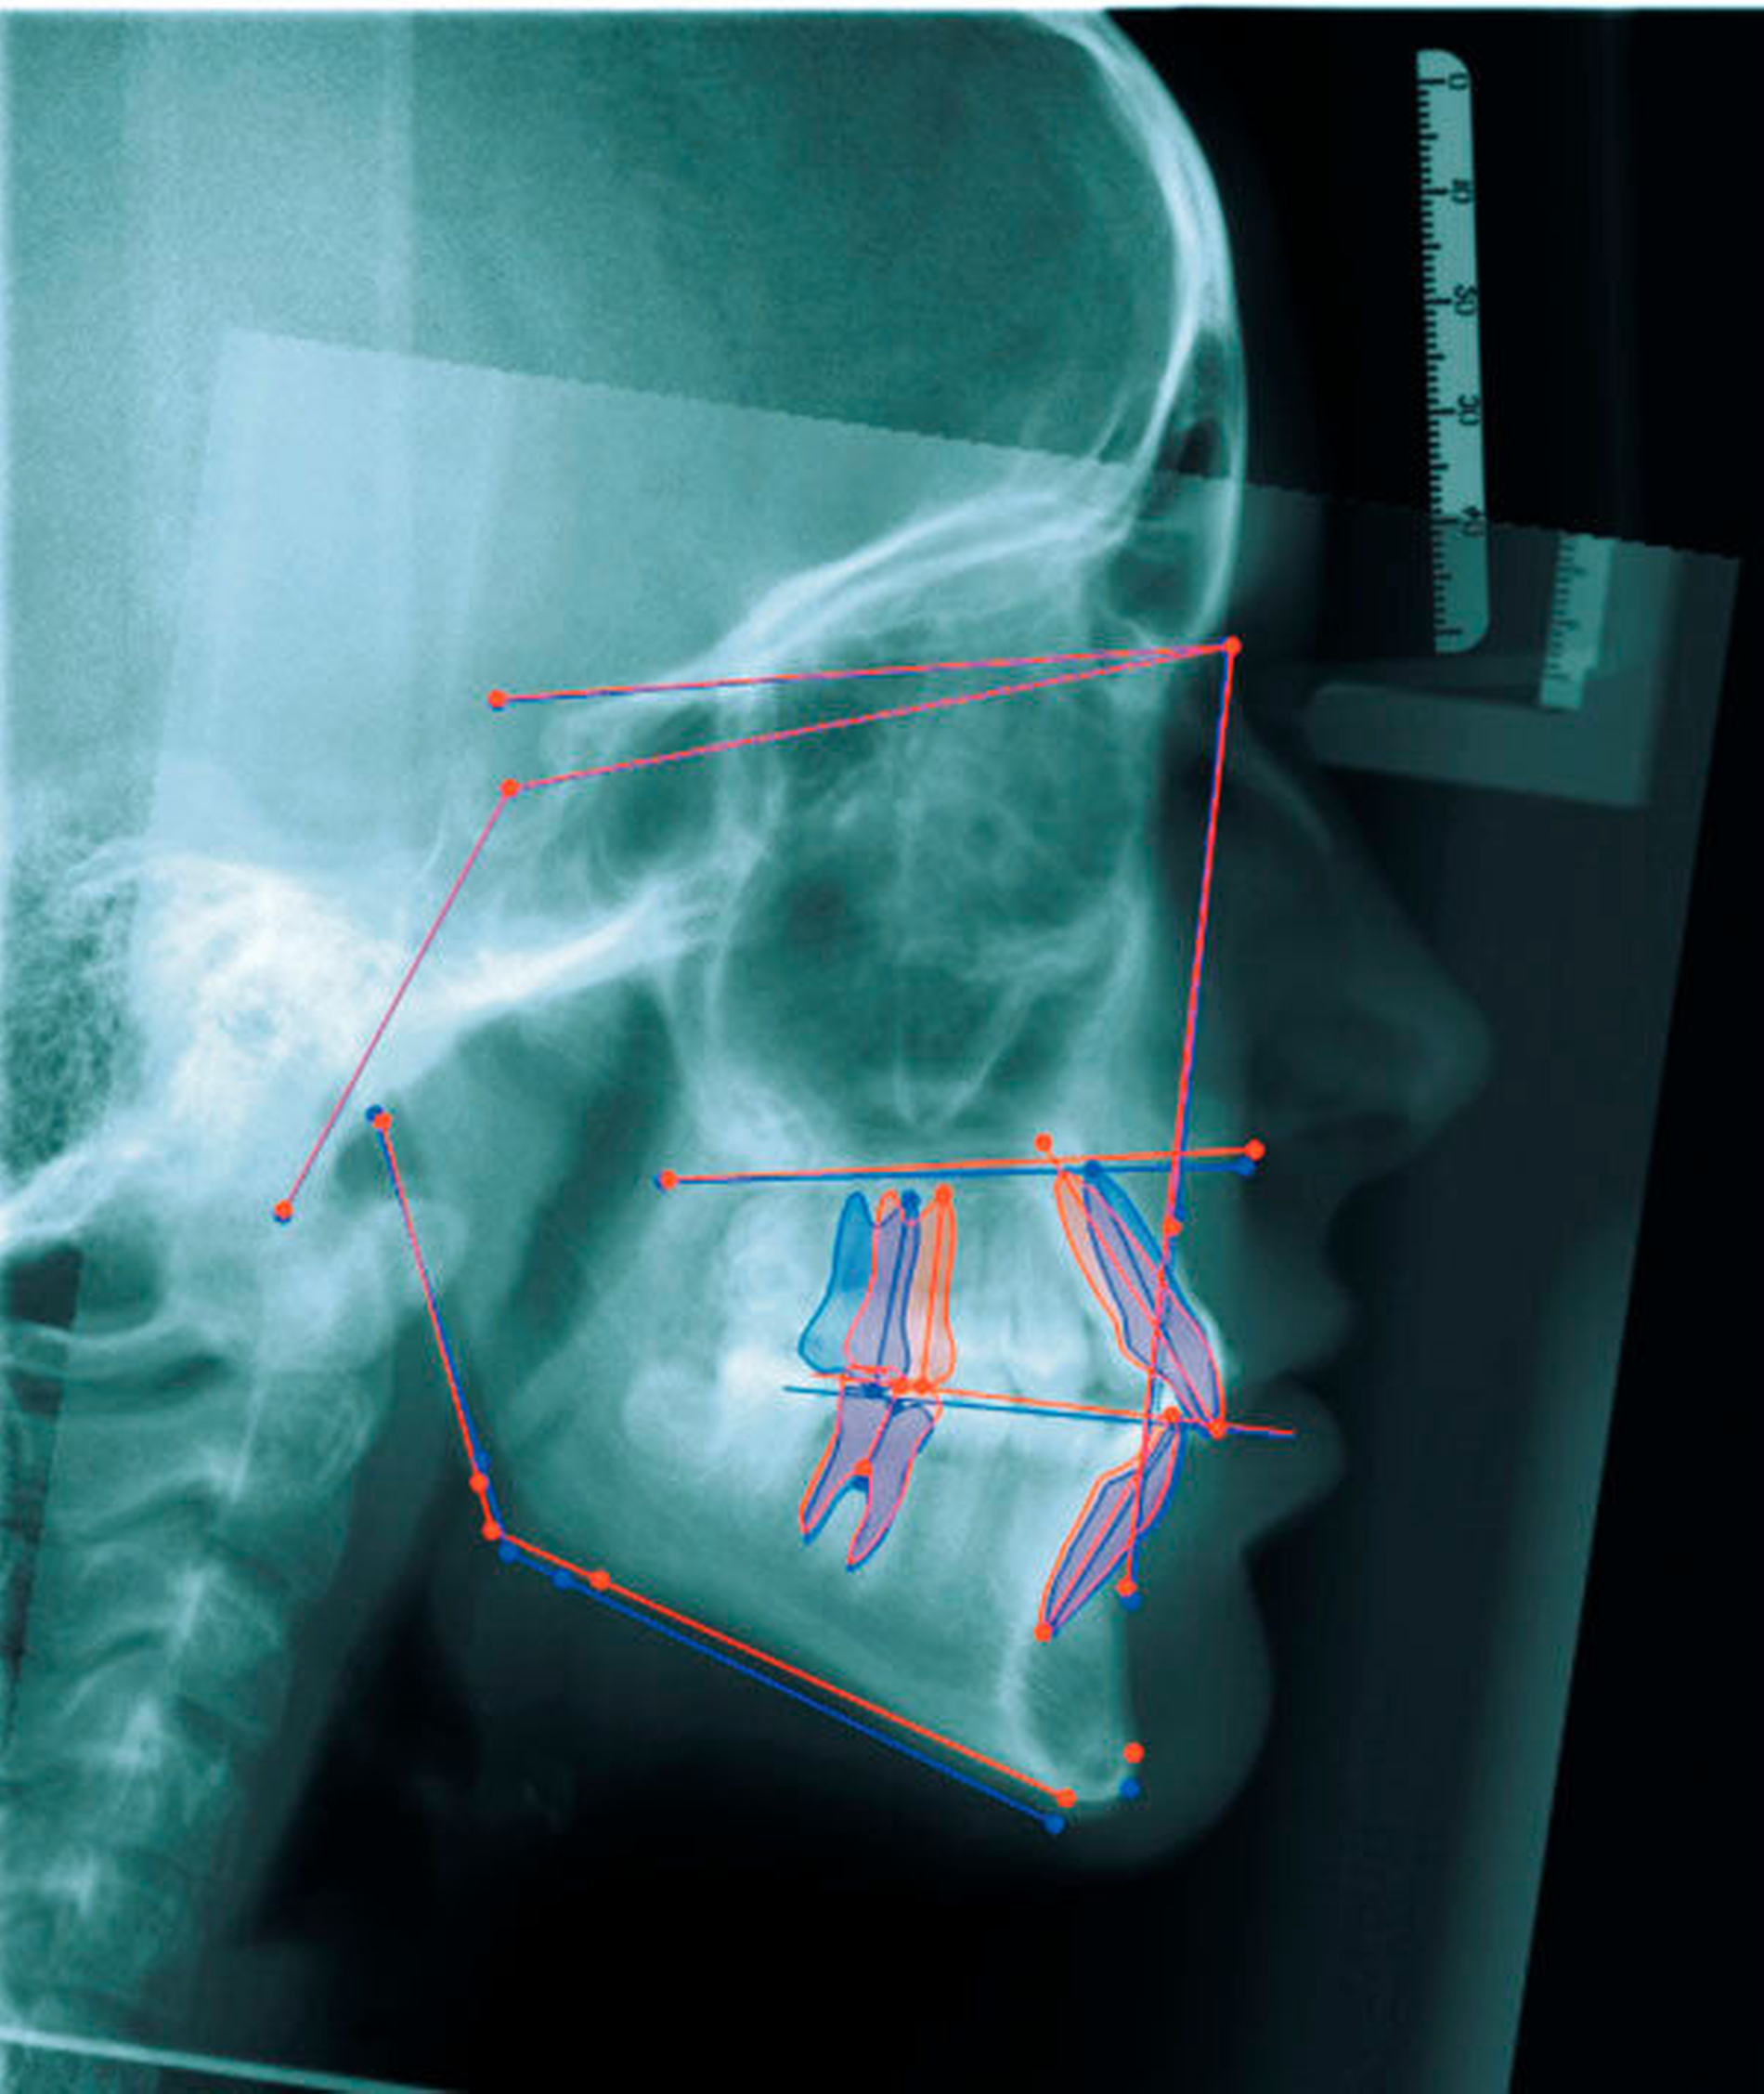

Wie beim Einbringen von Zahnimplantaten schaffen die computergestützte Planung und die Verwendung von Schablonen auch bei der Insertion von Mini-Implantaten mehr Sicherheit für den Behandlungserfolg. Für die zunächst virtuelle Insertion werden ein Abdruck oder ein Scan sowie ein Röntgenbild (FRS oder DVT) überlagert [De Gabriele, 2017] (Abbildungen 1 und 2, Easy Driver Software, Labor Uniontech, Parma/IT). Während in einem normalen Fall das FRS ausreicht, ist bei schwierigen Situationen (zum Beispiel LKG-Spalte, palatinal verlagerte Eckzähne) sicherlich die Anfertigung eines DVTs empfehlenswert. Basierend auf der computergestützten Planung wird eine Insertionsschablone per Rapid-Prototyping-Verfahren (RKS Labor, Rastede/D, Abbildung 3) zusammen mit dem gewünschten kieferorthopädischen Gerät im zahntechnischen Labor hergestellt.

Das Prinzip einer CAD/CAM-gesteuerten Insertion wird anhand einer zehnjährigen Patientin mit einem Platzmangel für die oberen Eckzähne dargestellt (Abbildungen 4a, 4b). Die Behandlung begann mit dem Anpassen von Molarenbändern und einem Silikon-Abdruck des Oberkiefers, der mit dem FRS an das zahntechnische Labor gesendet wurde und dort mit dem FRS der Patientin überlagert wurde. So konnten geeignete Insertionsstellen virtuell geplant werden (Abbildungen 1, 2a, 2b). Nach Rücksprache mit dem Behandler bezüglich der Mini-Implantatpositionen erfolgte die Herstellung der Insertionsschablone (Abbildung 3). Parallel dazu wurde auch der Beneslider [Wilmes, 2010] hergestellt, der zusammen mit der Insertionsschablone geliefert wurde (Abbildung 5). Mithilfe der Insertionsschablone konnten die Mini-Implantate und der Beneslider im selben Termin eingesetzt werden (Abbildungen 6, 7a, 7b). Nach 10 Monaten Distalisierung waren die Molaren in der Zielposition und es war ausreichend Platz für die Eckzähne vorhanden (Abbildungen 8a, 8b), so dass Brackets für die zweite Phase der Behandlung eingesetzt werden konnten. Die Multibracket-Apparatur (Abbildung 9) konnte nach 12 Monaten entfernt werden (Abbildungen 10, 11).